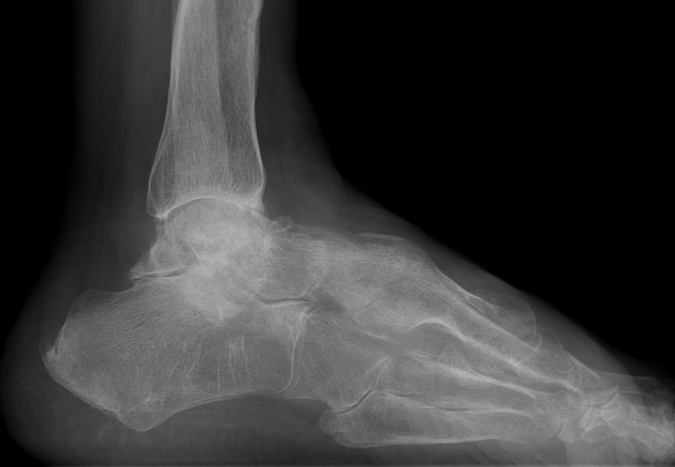

Combined ankle and subtalar joint osteoarthritis

Talar AVN

Trauma

Severe Deformity - acquired flat foot / neurological conditions / Charcot /

Rheumatoid arthritis

Severe acquired planovalgus

Fragility fractures